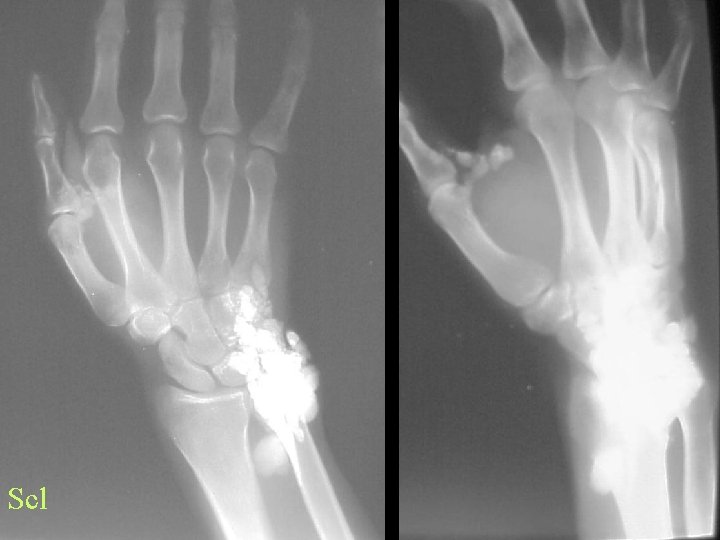

Scleroderma • Hands and pressure areas • Acro-osteolysis • Soft tissue changes • Subluxations

Scl